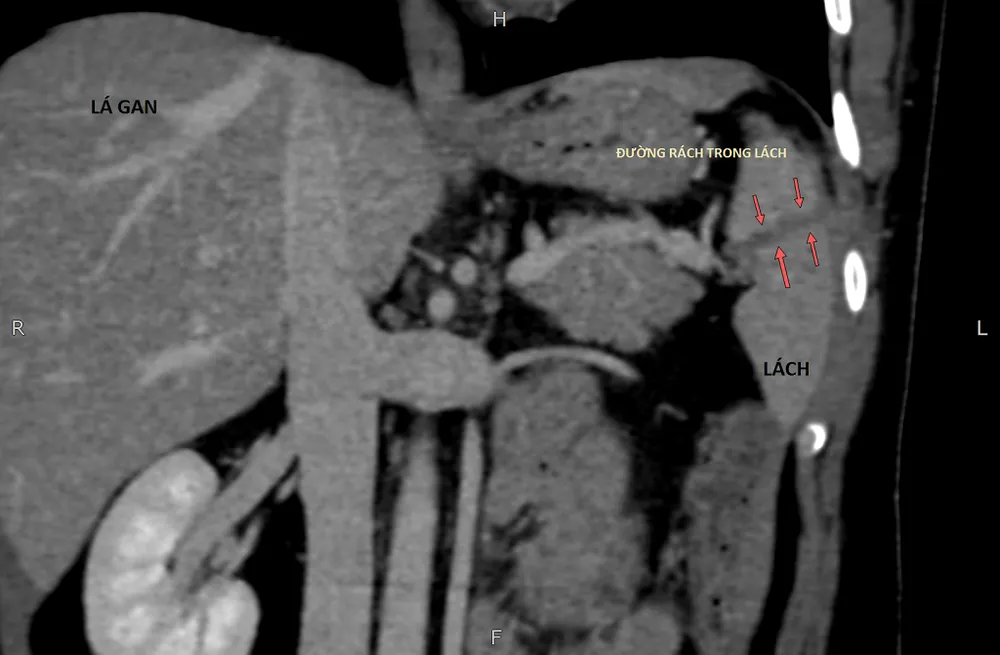

Bệnh nhân được các BS thăm khám, thử máu, siêu âm, chụp MSCT bụng, với chẩn đoán vỡ lách độ 3 gây chảy máu nhiều trong ổ bụng. Êkip BS đã nhanh chóng hội chẩn và quyết định điều trị với phương pháp “nút động mạch lách”. Đây là phương pháp điều trị nội mạch dưới máy chụp mạch kỹ thuật số xóa nền. BS dùng một ống thông nhỏ đường kính 1-2 mm luồn từ vùng bẹn phải vào động mạch đùi, đưa lên động mạch chủ vào động mạch lách. Từ động mạch lách, BS sẽ bơm thuốc cản quang chụp toàn bộ hệ động mạch của lách, tìm đến động mạch bị vỡ gây chảy máu ổ bụng. Sau khi xác định được mạch máu bị tổn thương, thuốc tắc mạch sẽ được bơm vào động mạch bị vỡ để cầm máu và giúp lành vết thương. Thủ thuật được thực hiện thành công trong vòng 30 phút.

Phần lách bị vỡ